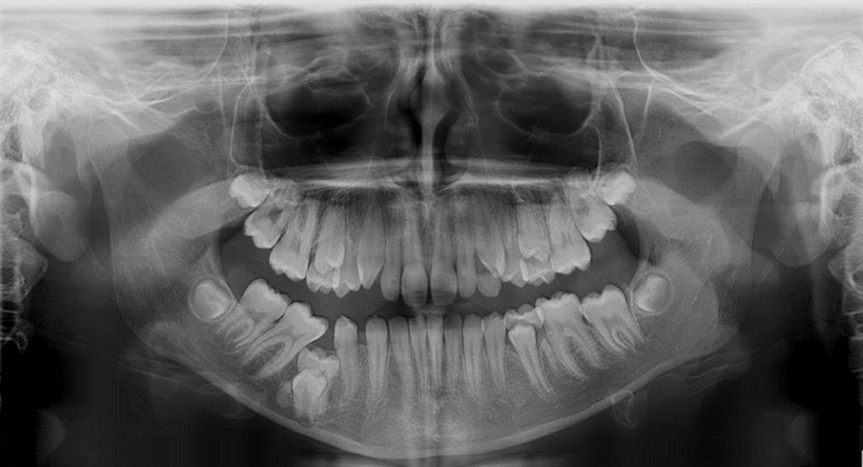

Paziente di anni 12 e 7 mesi.

L’odontoiatra, eseguita la visita iniziale per eventuale trattamento ortodontico, ha rilevato l’assenza in arcata di 45.

La dentizione della paziente risulta mista per permanenza in arcata di elementi decidui.

La radiografia panoramica ha messo in evidenza l’incarceramento di 85 che ha determinato a sua volta il completo incarceramento della gemma di 45, distalmente alla quale si evidenzia la presenza di piccola isola di compatta senza significato patologico attuale.

L’inclusione di tale elemento ha portato alla mesializzazione dei molari contigui (46 e 47) e alla migrazione distale di 44 creando un diastema 43-44.

Altra piccola calcificazione lineare si rileva distalmente a 35, anch’esso incluso, compatibile con la radice distale dell’omologo deciduo fratturata.

In questi casi, a giudizio clinico, sarebbe utile un approfondimento di indagine con TC Cone Beam dell’arcata inferiore per evidenziare la corretta localizzazione degli elementi inclusi in rapporto al canale mandibolare.

Per la corretta localizzazione spaziale di 48 e 49 ed i loro rapporti con il canale alveolare è necessario approfondimento di indagine con TC cone beam.